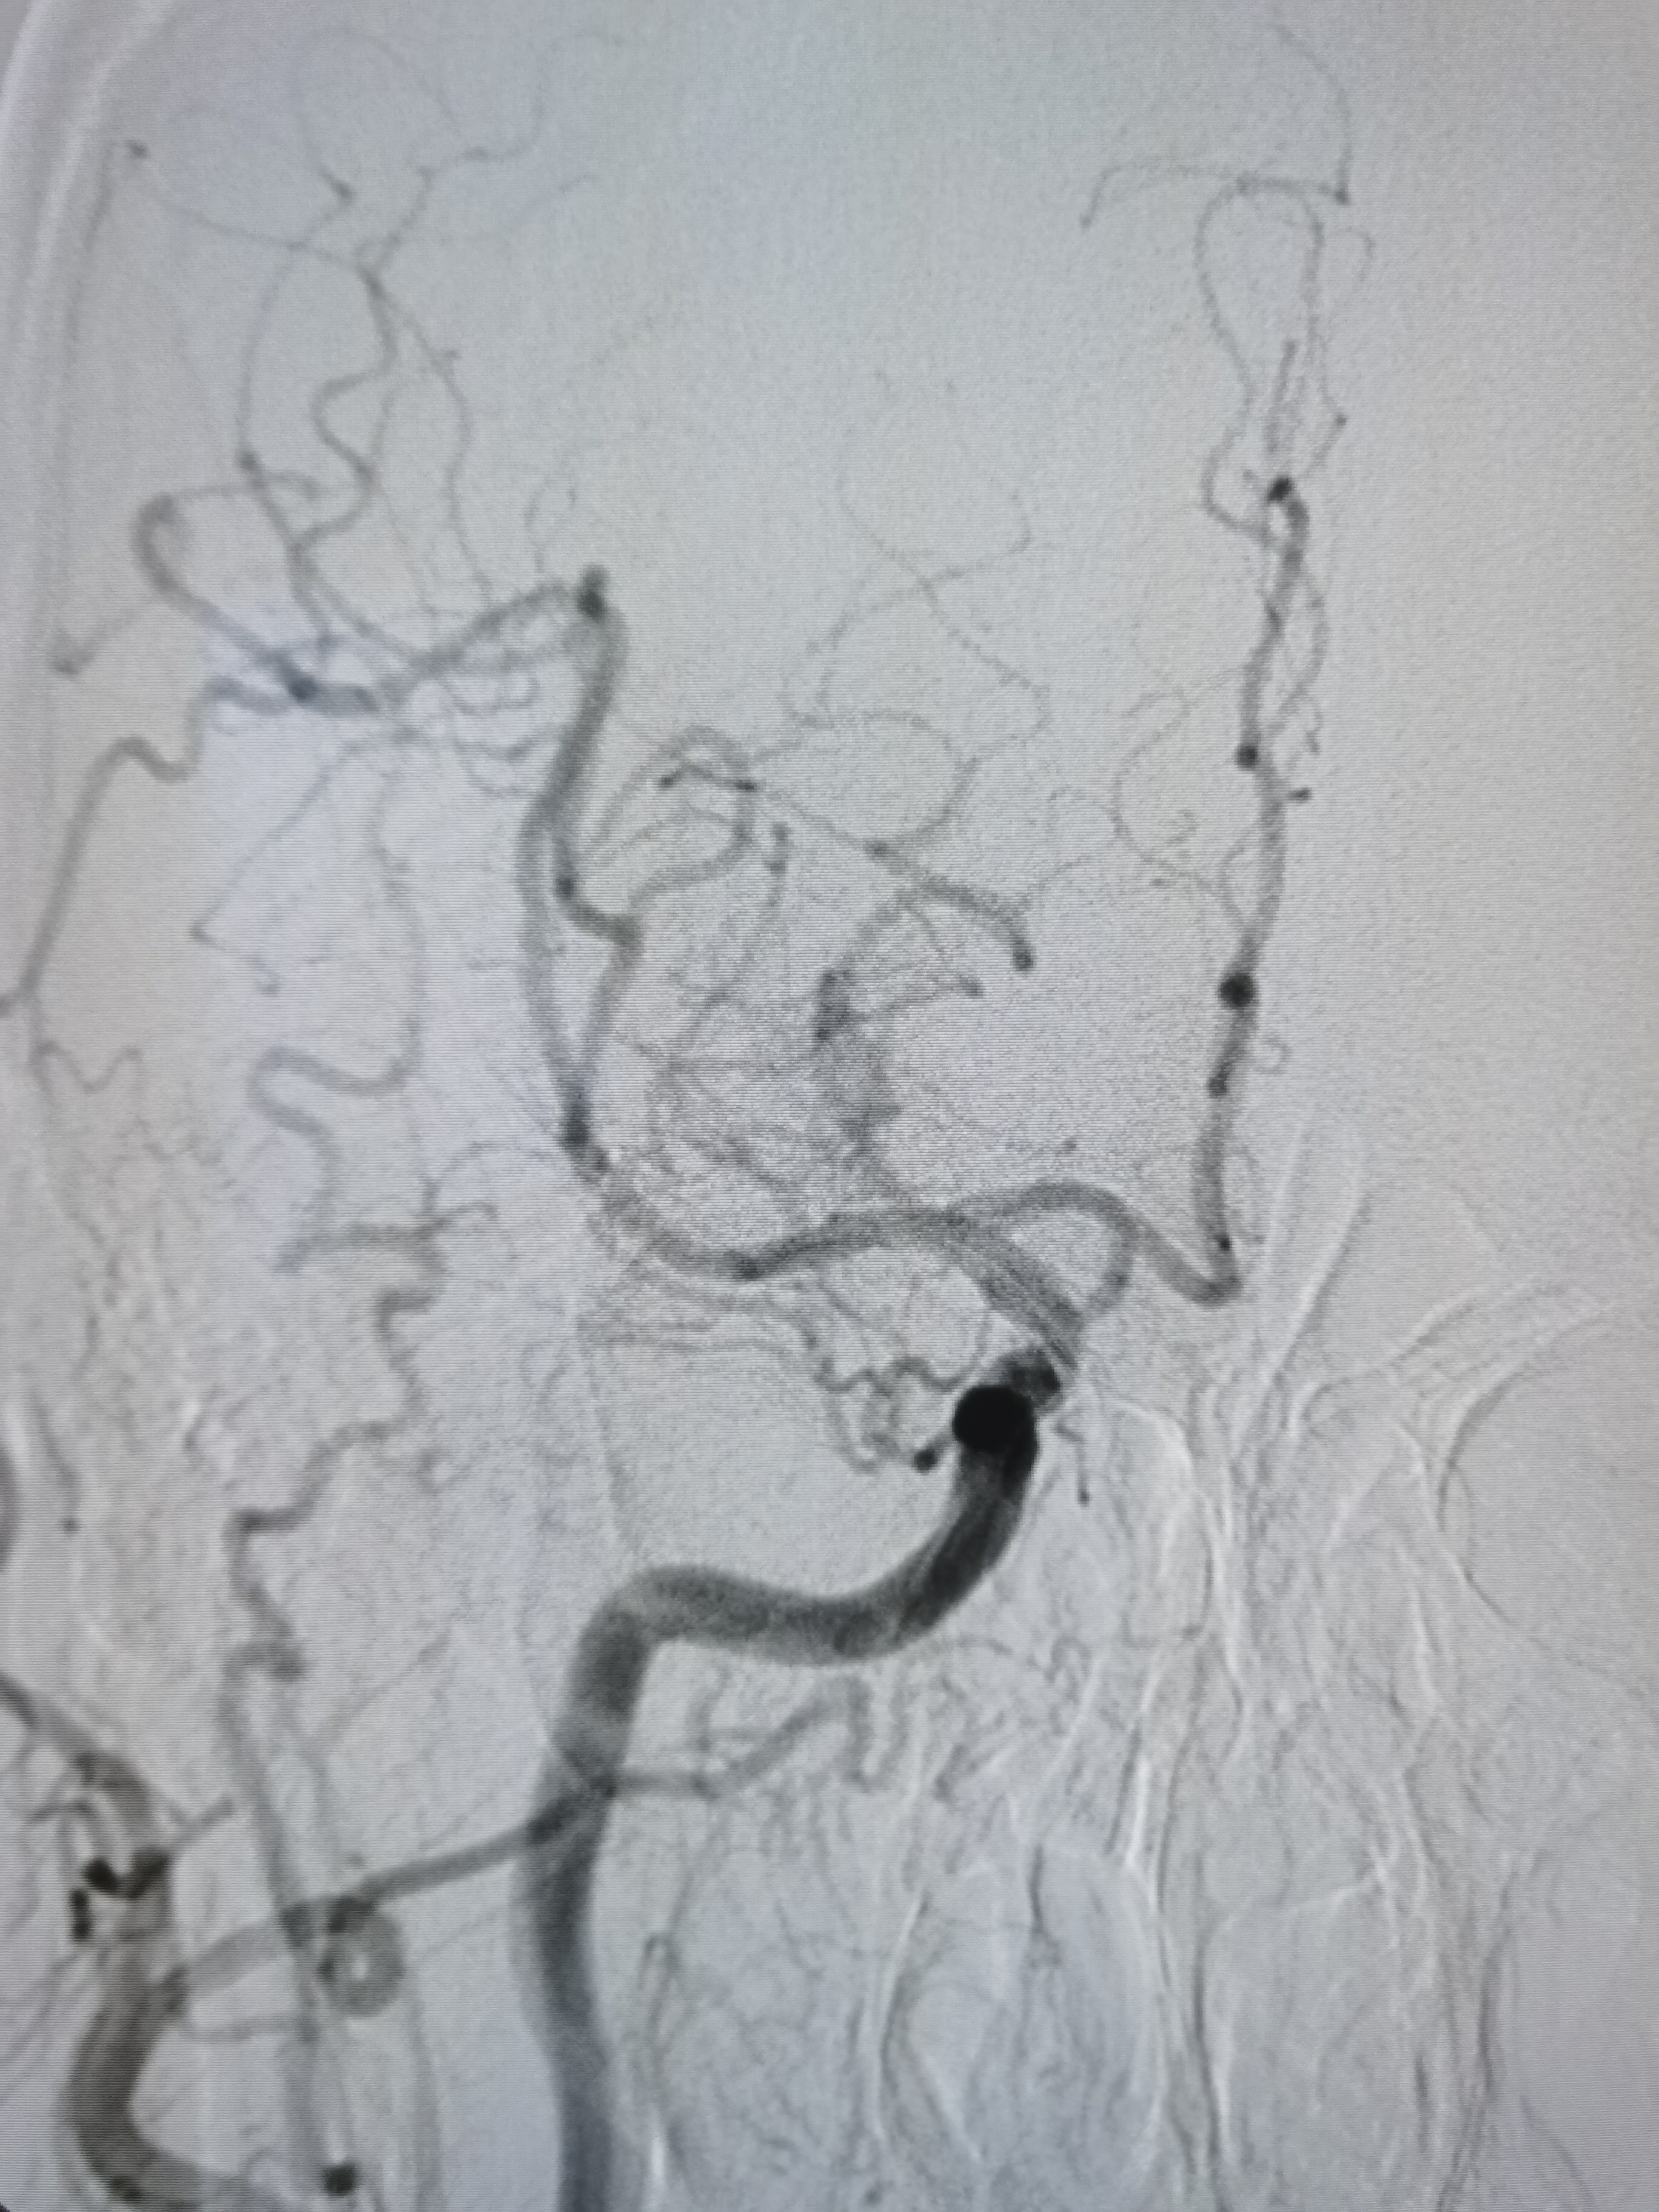

左侧胚胎型大脑后动脉,颅内血流明显改善。

支架位置形态满意,撤出保护伞,结束手术。

术前术后对比